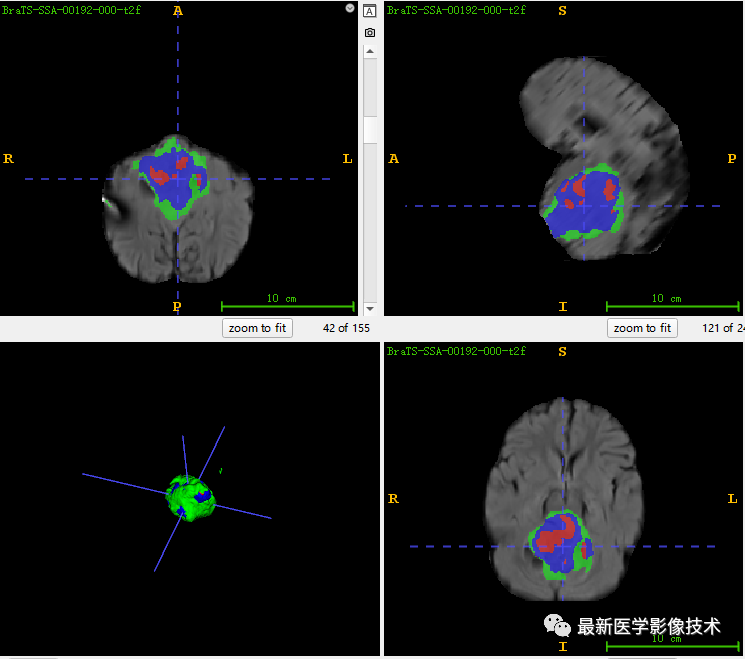

6、验证集分割结果

左图是金标准结果,右图是网络预测结果。

7、测试集分割结果